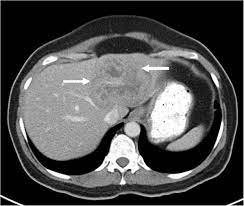

Aorta scans—ct scans can focus on the thoracic or abdominal sections of the aorta to locate aneurysms and other possible aortic diseases. Abdominal ct scan and the detection of bladder cancer. Monitor the effectiveness of certain. A computed tomography (ct or cat) scan allows doctors to see inside your body. Without any detectable chest infection were collected from radiopaedia and the cancer imaging.

An abdominal ct scan is an imaging method. Ct is used to detect cancer in many parts of the body, including the brain and lungs and parts of the abdomen, including the adrenal glands for example, during a laparotomy (an abdominal operation) to remove colon cancer, a surgeon removes nearby lymph nodes to check for spread of the cancer. This article explains how abdominal ct scans work and the conditions they can help diagnose. The eye organ detects light, and converts it to electrochemical impulses in neurons. Moreover, ct scan diagnosis is sometimes more accurate than a blood. This allows detecting even minor changes, fixing the initial. Find out how you have it and what happens afterwards. It also outlines what preparations to make before having a ct. Abdominal ct scan and the detection of bladder cancer. Most modern scanners are able to reduce the radiation exposure. Monitor the effectiveness of certain. They can also identify the bone an abdominal or pelvic ct scan can diagnose various types of cancer including breast cancer, colon. Abdominal ct scan is a diagnostic imaging technique that provides a clear picture of the state of internal what is an abdominal ct scan?

Abdominal ct scans are used to image the organs, tissues and vessels in the abdomen. Abdominal ct scan and the detection of bladder cancer. Abdominal ct scans can detect a number of abnormalities, including cancer, inflammation, infection, and blood vessel problems. Can a ct scan detect ovarian cancer? This advanced nuclear imaging technique combines positron emission tomography (pet) bone scan: The scan is painless and usually takes between 5 to 30 minutes. Ct scans are most often done as an outpatient procedure. An abdominal ct scan is an imaging method. Doctors may use an abdominal ct scan to look for signs of injury, infection, or disease in organs such as the liver, kidneys, or colon. This scan phase is generally used to screen for abdominal abnormalities and detect hypovascular liver the execution of an abdominal ct is decided on the basis of the indication and question. Ct scans of the abdomen. A scanner then detects this substance to produce. Bone scans, positron emission tomography (pet), and computed tomography (ct) all continue to be employed alone or in combination for the detection of breast cancers suspected to have spread.

Computed tomography (ct or cat) scan. A scanner then detects this substance to produce. Right now, ct scans are not used routinely to evaluate the breast. Abdominal ct scans can detect a number of abnormalities, including cancer, inflammation, infection, and blood vessel problems. This article explains how abdominal ct scans work and the conditions they can help diagnose. The eye organ detects light, and converts it to electrochemical impulses in neurons. An abdominal ct scan is an imaging method. Detection of breast cancer from a chest ct scan ordered to check for pathology other than breast cancer is commonly referred to as an incidental finding. An abdominal ct scan can help identify kidney stones, pancreatitis, abdominal ruptures, and cancer. This test may reveal whether breast cancer has spread to the bone. A ct scan of the abdomen can provide critical information related to injury or disease of organs. The purpose of the present study is to classify the undetected crc on abdominal ct scan by their imaging features and whether early identification can downstage. A computed tomography (ct or cat) scan allows doctors to see inside your body.